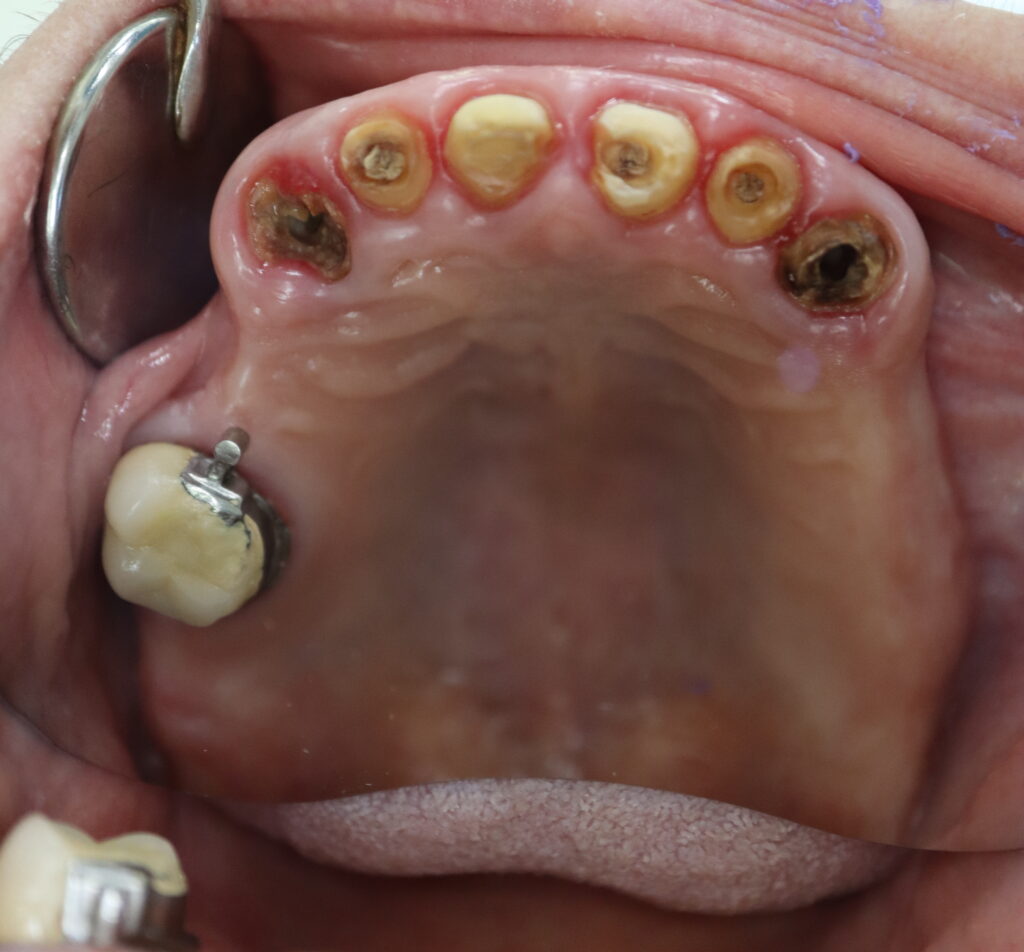

Ситуация до лечения

пациент до имплантации